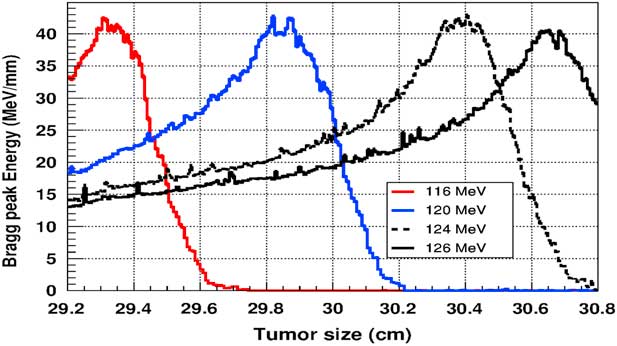

Figure 5 shows the plot of the deposited energy of a monoenergetic proton beam along the tumour size. As this figure shows, to surround completely a such tumour we should use a proton beam energy, ranging between 116 and 126 MeV. For this range energy, the Bragg peak energy is around 40 MeV and the half-value width for each Bragg peak is about 50% of the tumour size. The effect of adding gold in the tumour on the Bragg peak energy is shown in Figure 6. In this figure, we notice that the Bragg peak is localised in the tumour for the proton beam energy ranging between 116 and 130 MeV. The Bragg peak energy at the centre of the tumour is greater than without GNPs, in this case, with the presence of GNPs, the proton therapy is enhanced up to 75%, this is due to the concentration of GNPs at the centre of the tumour. Moreover, for high proton beam energy like 130 MeV, the width at half height of the Bragg peak is around of 75% of the tumour size. Comparing with previous results, the presence of GNPs in the tumour makes the width at half height of Bragg peak larger. This result shows that adding GNPs in tumours makes the proton therapy easier in clinical medicine and presents more benefit. Similarly in Figure 7, we plotted the deposited energy in the tumour with the presence of nanoplatinum materials. In this figure, the Bragg peak is localised in the tumour for the proton beam energy ranging between 116 and 132 MeV. Comparing with previous results, the width at half height of the Bragg peak is spread over 85% of the tumour. Moreover, the deposited energy at the centre in the tumour is almost double comparing with the same results in Figure 6. In the case of the use of silver NPs during this therapy, the plot of the deposited energy has the same shape as in the case of the use of GNPs (see Figure 8).

Figure 5 The deposited energy of a monoenergetic proton beam into a spherical tumour with a diameter of 1·5 cm. Notes: The proton beam energy is ranging between 116 and 126 MeV.